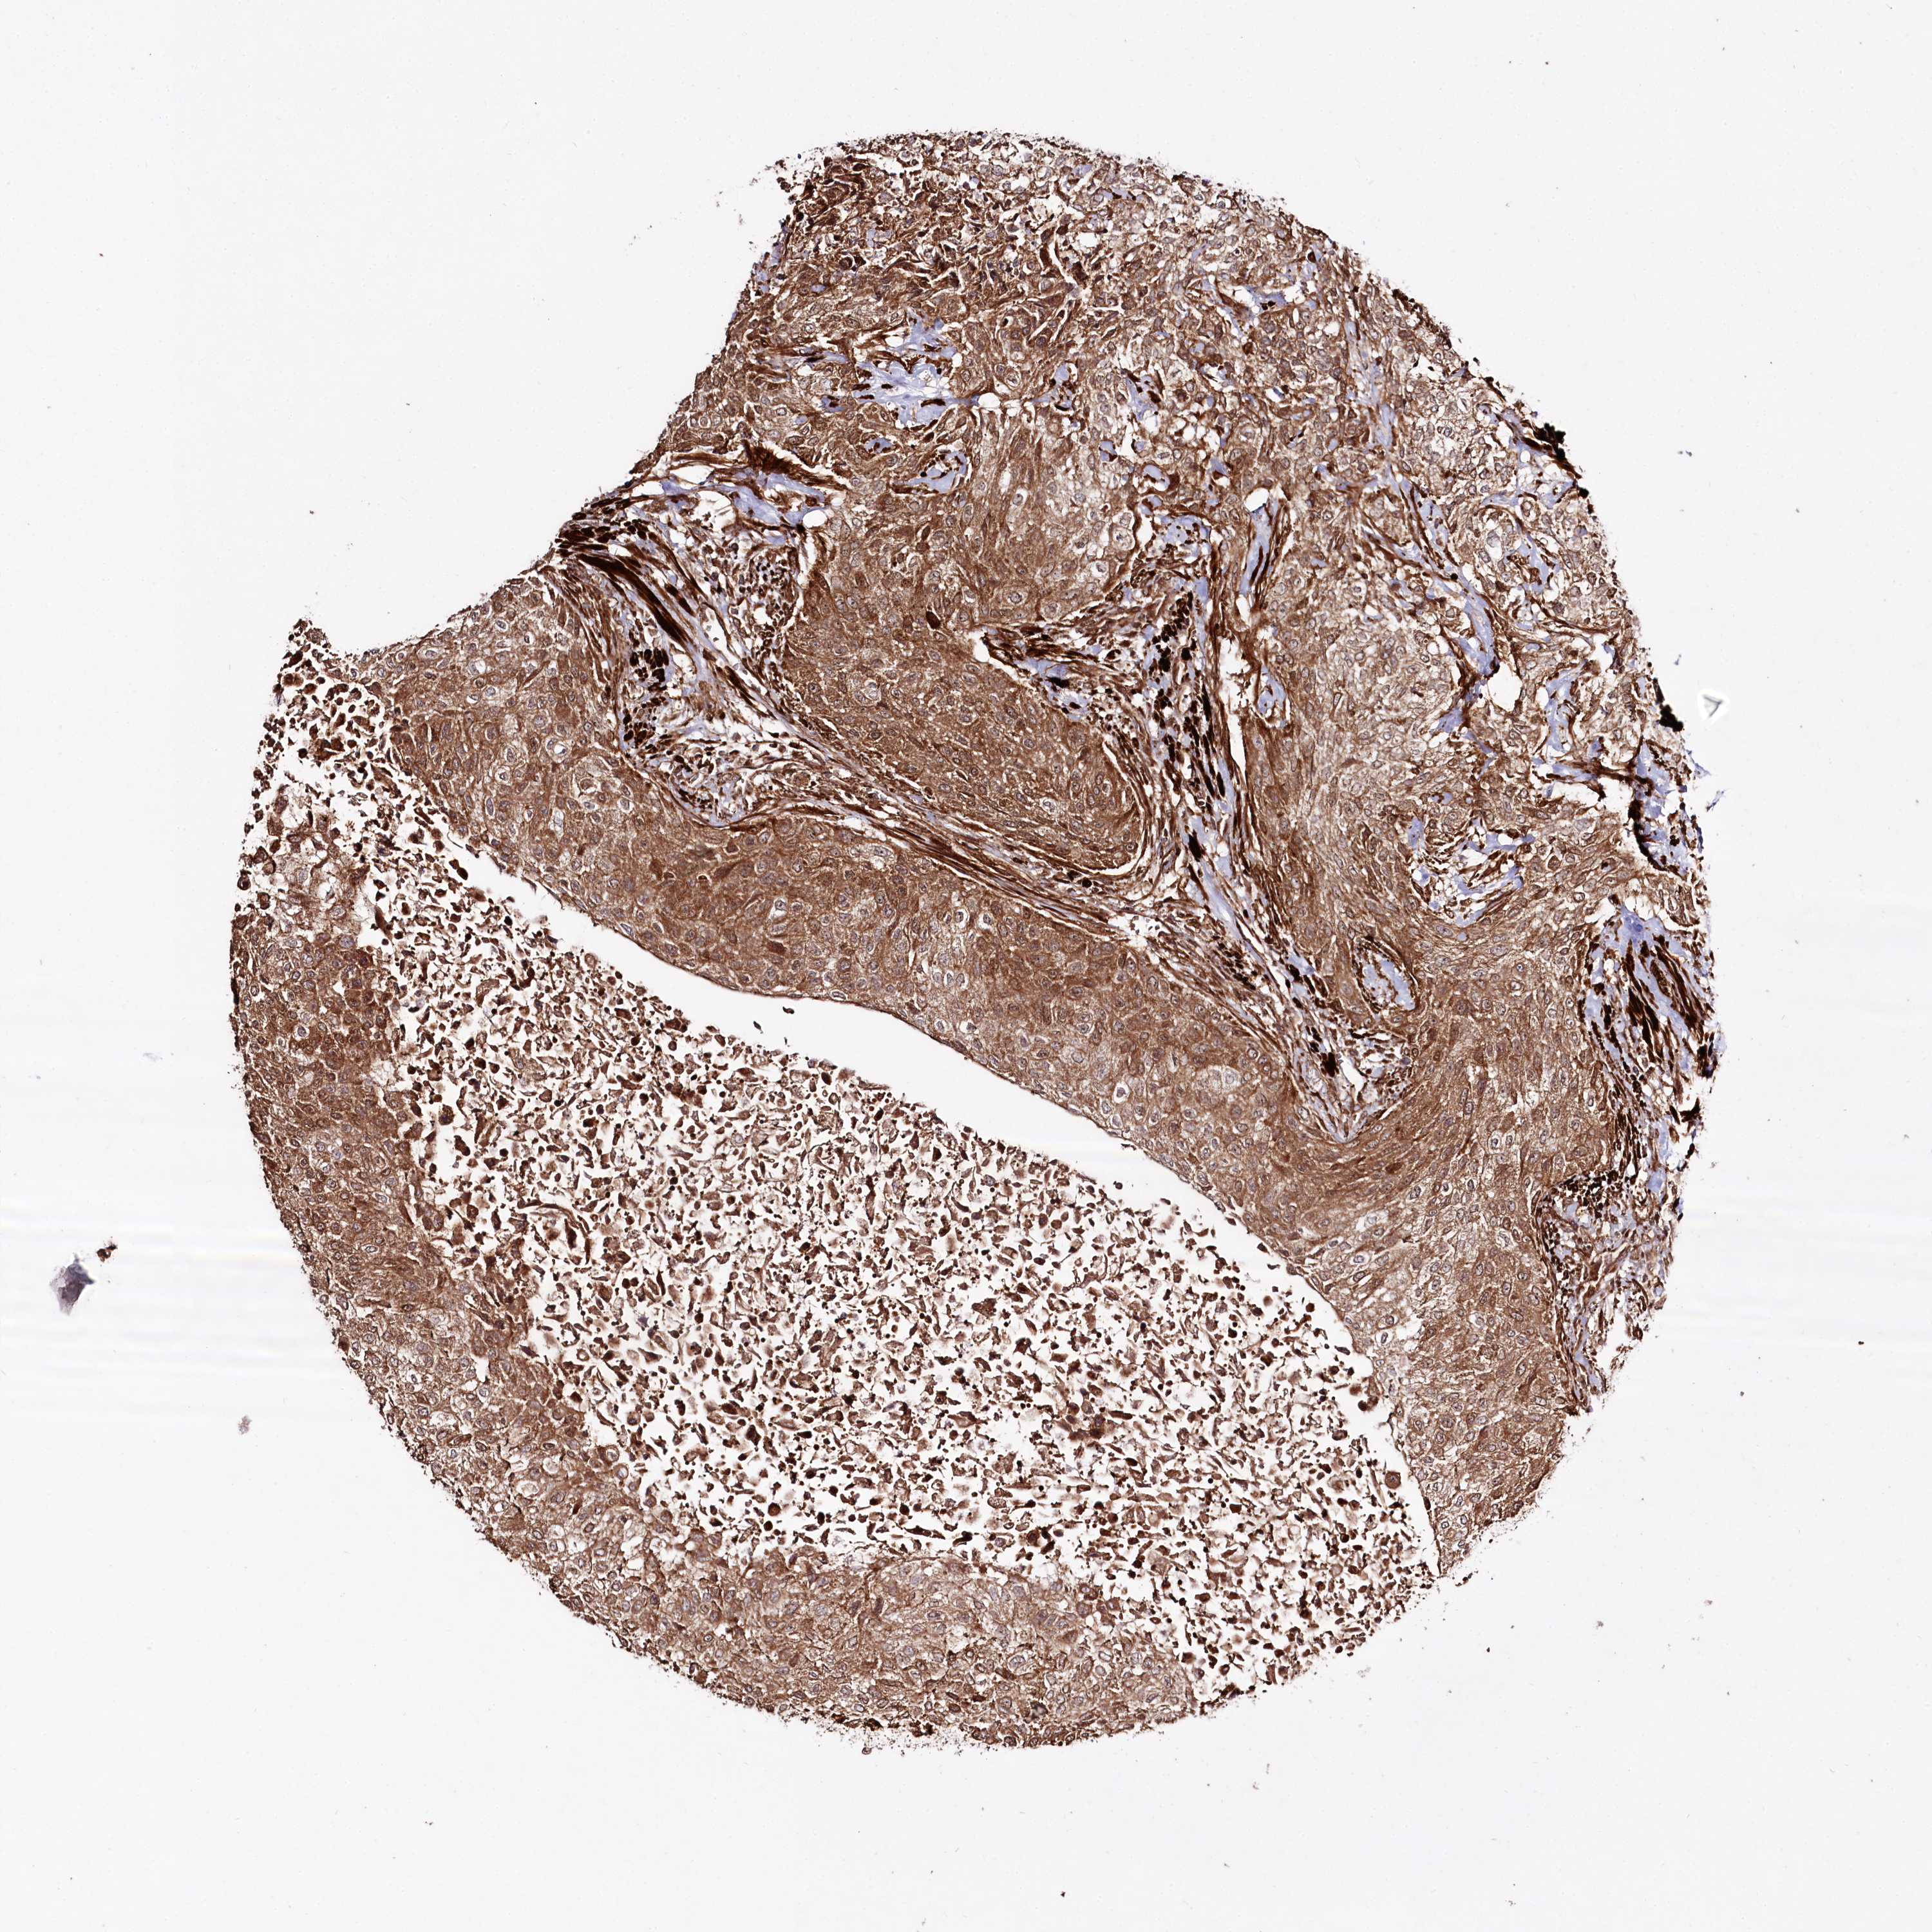

UROTHELIAL CANCER - Protein expressioni

A mouse-over function shows sample information and annotation data. Click on an image to view it in a full screen mode. Samples can be filtered based on level of antibody staining by selecting one or several of the following categories: high, medium, low and not detected. The assay and annotation is described here.

Note that samples used for immunohistochemistry by the Human Protein Atlas do not correspond to samples in the TCGA dataset.

Antibody stainingi

Antibody staining in the annotated cell types in the current human tissue is reported as not detected, low, medium, or high, based on conventional immunohistochemistry profiling in selected tissues. This score is based on the combination of the staining intensity and fraction of stained cells.

Each image is clickable and will lead to virtual microscopy that enables deeper exploration of all samples and also displays staining intensity scores, fraction scores and subcellular localization as well as patient and tissue information for each sample.

Antibody HPA038450

Antibody HPA038451

Staining

High

Medium

Low

Not detected

Intensity

Strong

Moderate

Weak

Negative

Quantity

>75%

75%-25%

<25%

None

Location

Nuclear

Cytoplasmic/membranous

Cytoplasmic/membranous,nuclear

Urothelial carcinoma, High grade

Urothelial carcinoma, Low grade

Urothelial carcinoma, NOS